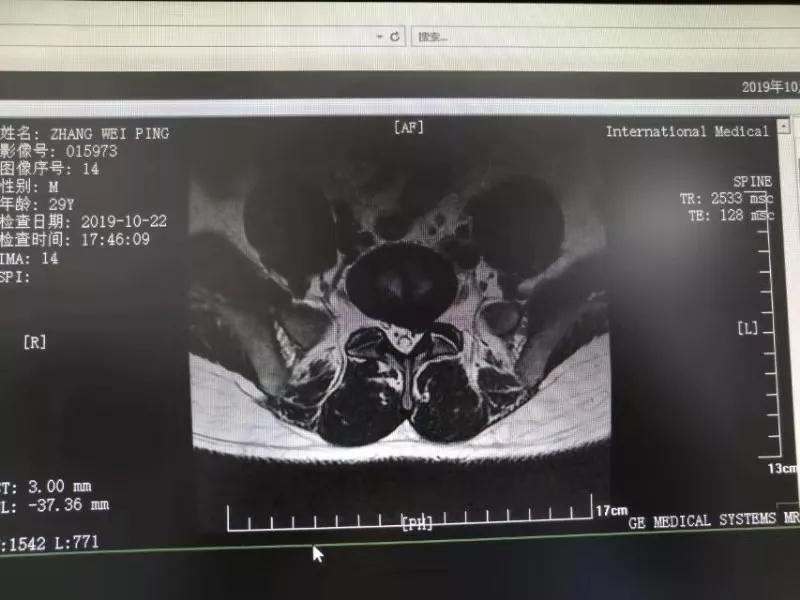

10月25日,29歲的患者小張了解到西安國(guó)際醫(yī)學(xué)中心骨科醫(yī)院專家云集,一大早便在家人的陪同下,來(lái)到西安國(guó)際醫(yī)學(xué)中心骨科醫(yī)院就診?!拔已闯掷m(xù)2年多,最近感冒后腰痛癥狀明顯加重了?!毙埫媛犊喑?,因?yàn)殚L(zhǎng)期腰痛、左下肢放射性疼痛,她晚上睡覺不能平躺,經(jīng)常疼得睡不著,需要口服止痛藥物才能有所緩解。走路走不了多遠(yuǎn)就開始腿抽的疼,嚴(yán)重影響到工作和生活。

結(jié)合患者的檢查以及年齡情況,王自立副院長(zhǎng)推薦讓專門研究椎間孔鏡技術(shù)王雄勛主任給小張做微創(chuàng)的椎間孔鏡手術(shù)。該手術(shù)創(chuàng)傷很小,不影響脊柱的穩(wěn)定性,尤其適合于椎間盤突出的年輕患者,懷著對(duì)骨科醫(yī)院專家的信任,小張與家人商議后,接受手術(shù)治療。